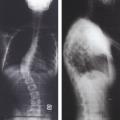

Mesure de gibbosité

SCLOLIOSE

Scoliose dorsale droite

SCOLIOSE

GIBBOSITE